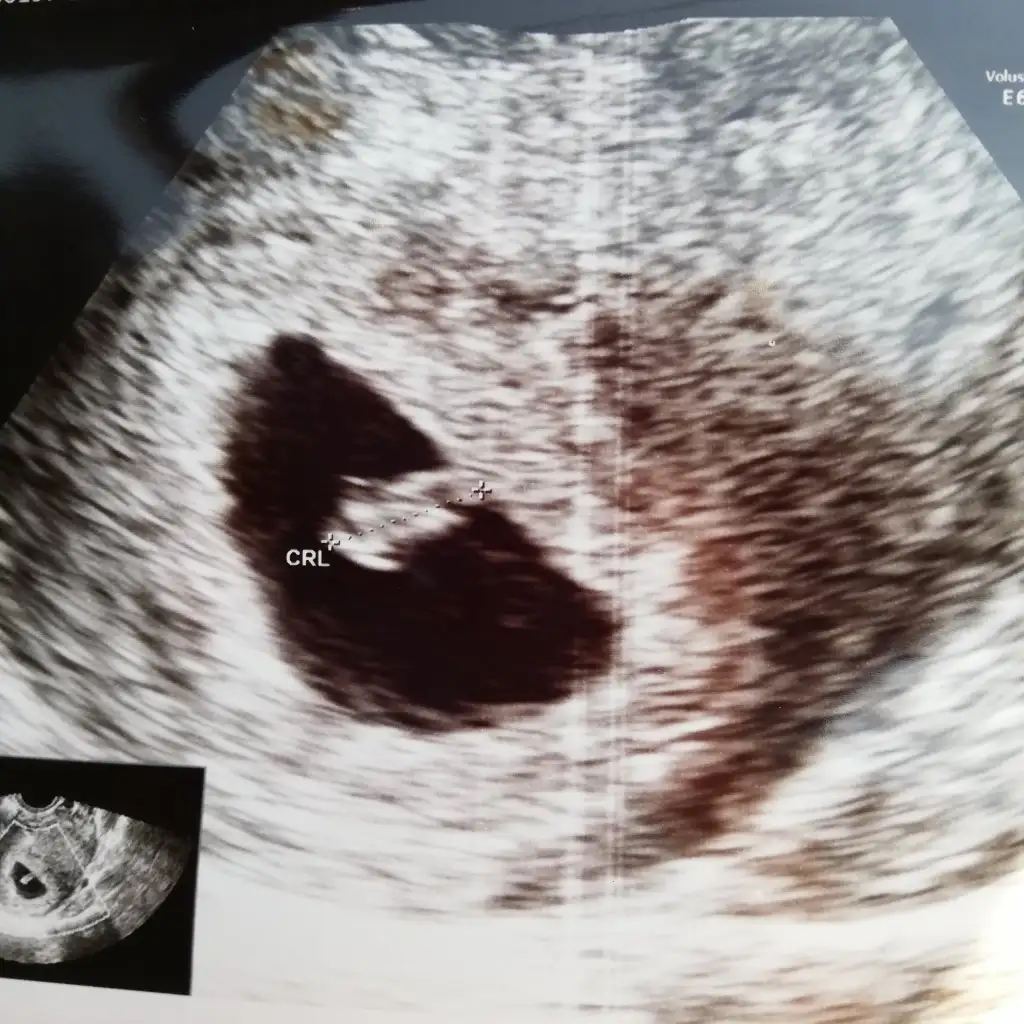

Canım bunada bakabilirmisin 7+6 günlük cinsiyeti nedir:) karından ultrasonKız buna göre ama en iyi 11 12 13 haftalar

Kız gibi ama en iyi 11 12 13 haftalar olmalıCanım bunada bakabilirmisin 7+6 günlük cinsiyeti nedir:) karından ultrason